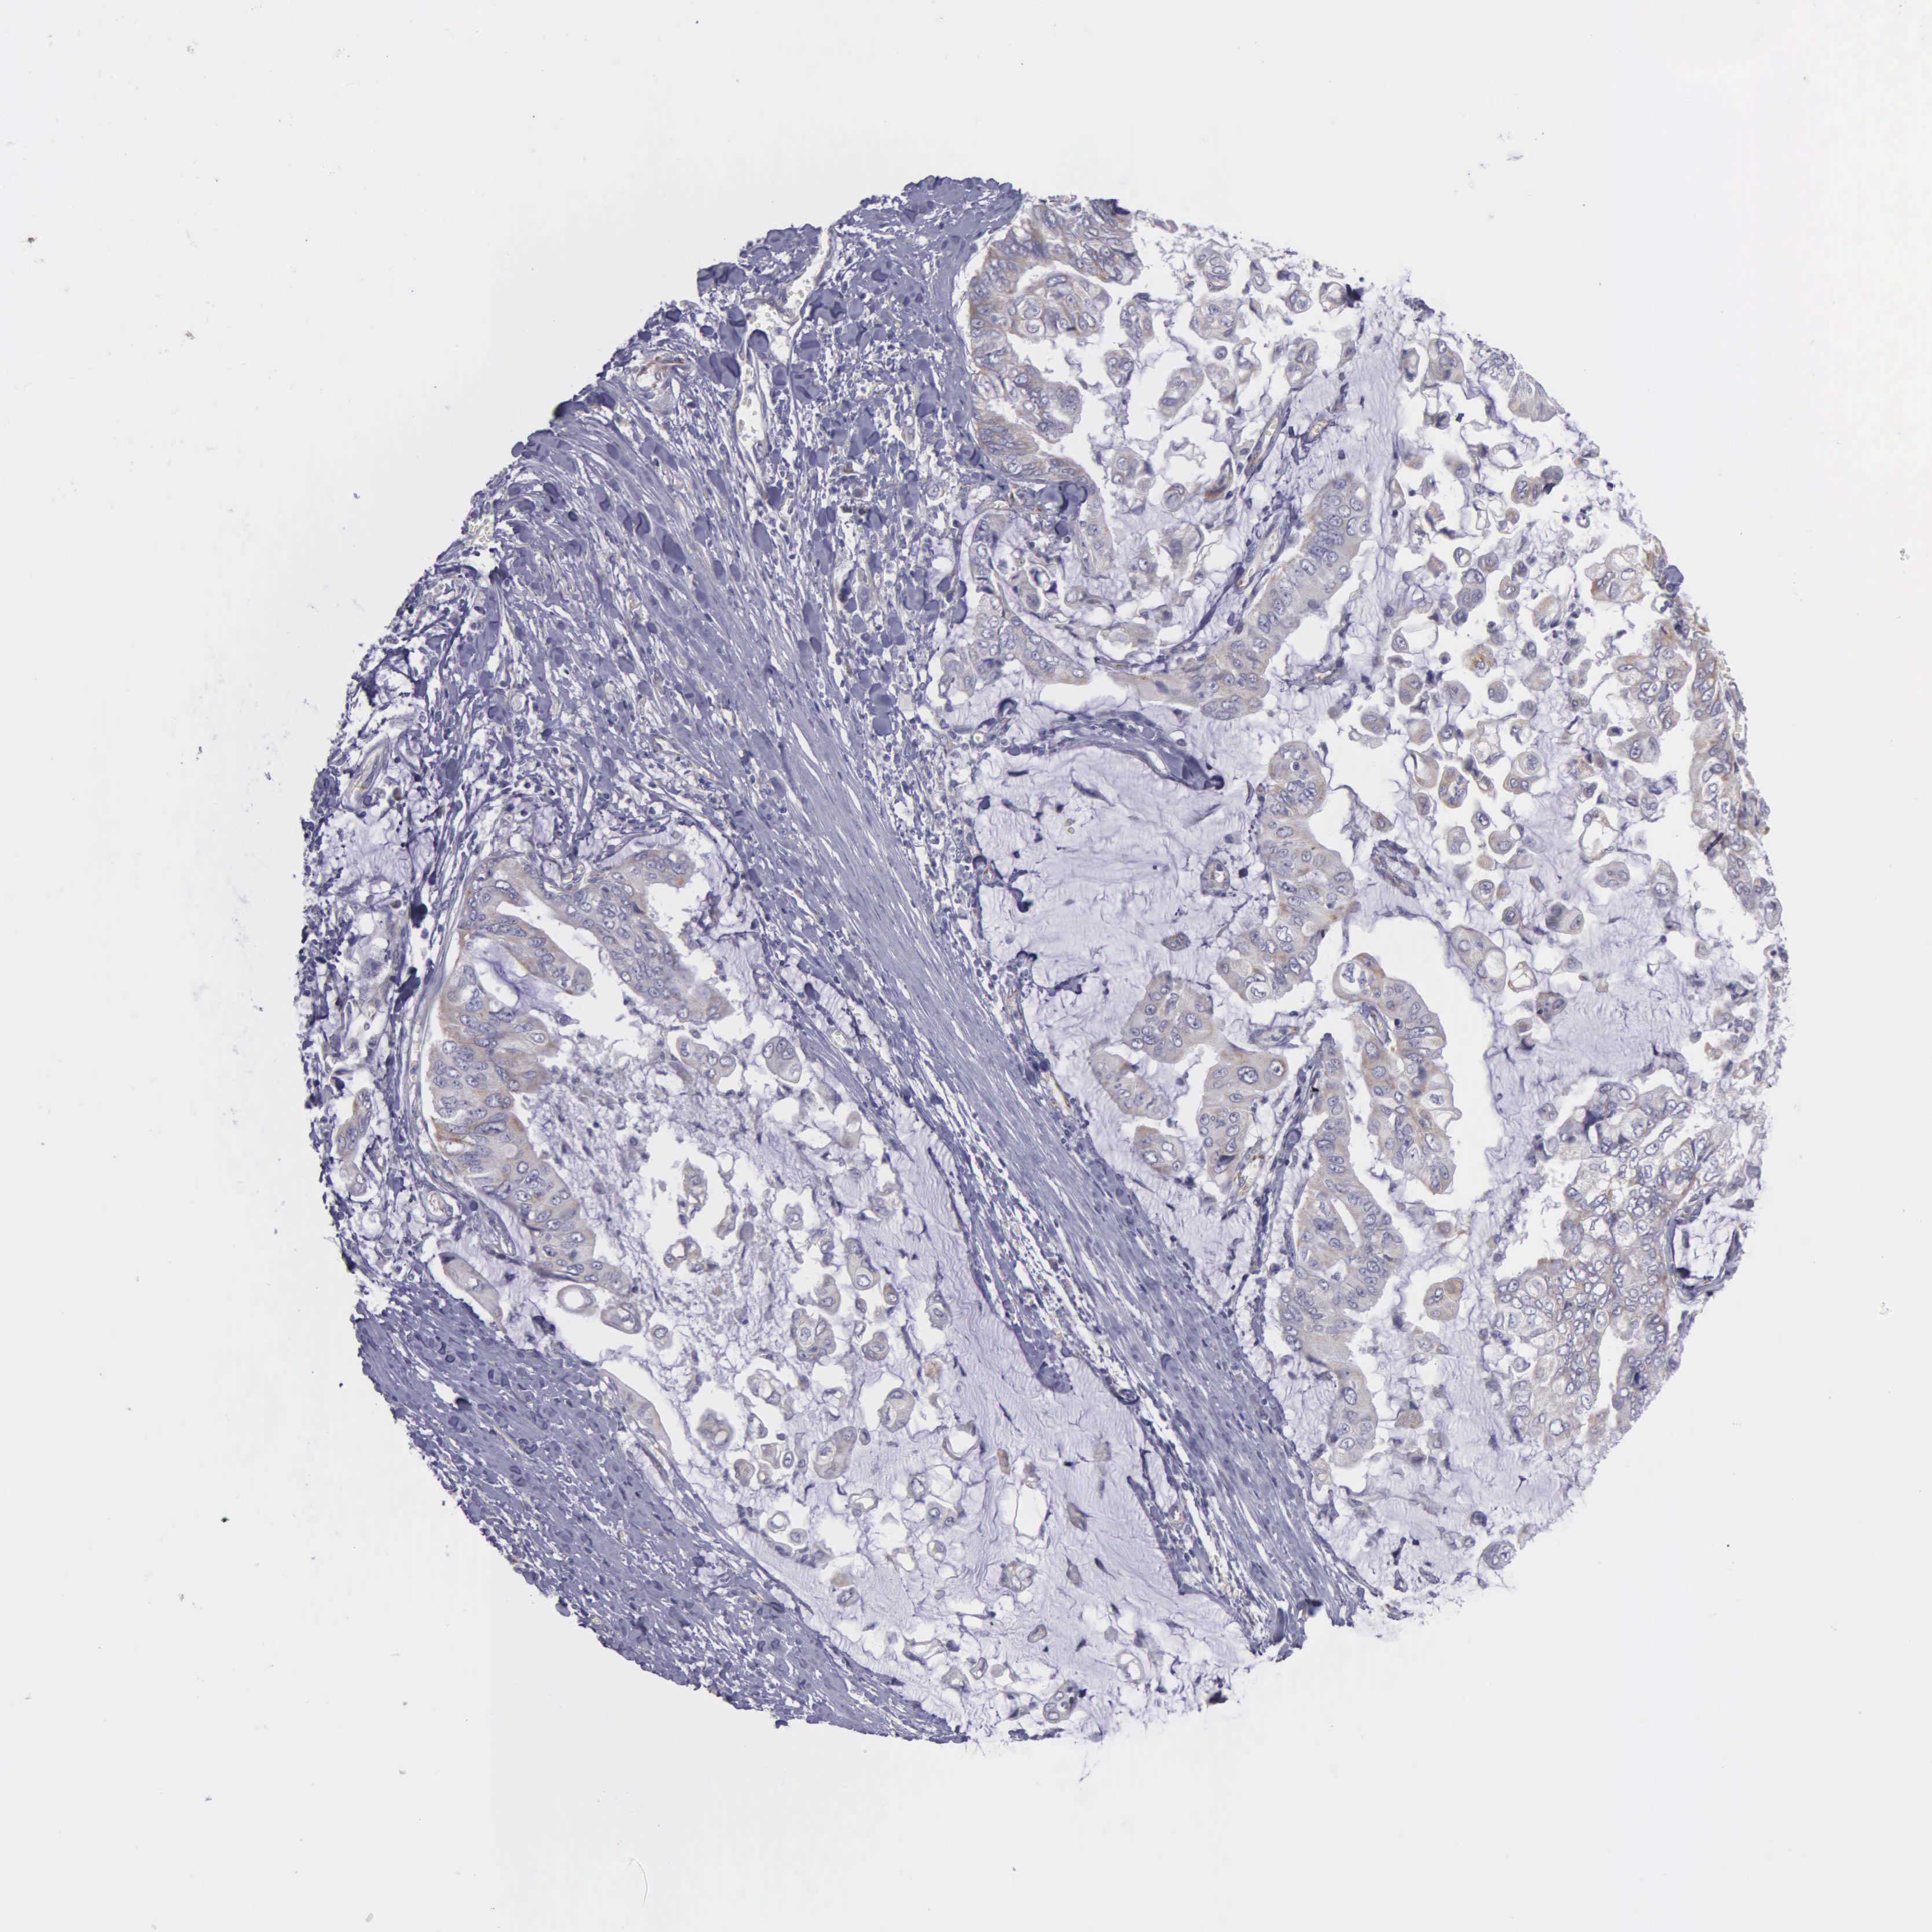

STOMACH CANCER - Protein expressioni

A mouse-over function shows sample information and annotation data. Click on an image to view it in a full screen mode. Samples can be filtered based on level of antibody staining by selecting one or several of the following categories: high, medium, low and not detected. The assay and annotation is described here.

Note that samples used for immunohistochemistry by the Human Protein Atlas do not correspond to samples in the TCGA dataset.

Antibody stainingi

Antibody staining in the annotated cell types in the current human tissue is reported as not detected, low, medium, or high, based on conventional immunohistochemistry profiling in selected tissues. This score is based on the combination of the staining intensity and fraction of stained cells.

Each image is clickable and will lead to virtual microscopy that enables deeper exploration of all samples and also displays staining intensity scores, fraction scores and subcellular localization as well as patient and tissue information for each sample.

Antibody HPA000866

Antibody HPA062659

Staining

High

Medium

Low

Not detected

Adenocarcinoma, NOS